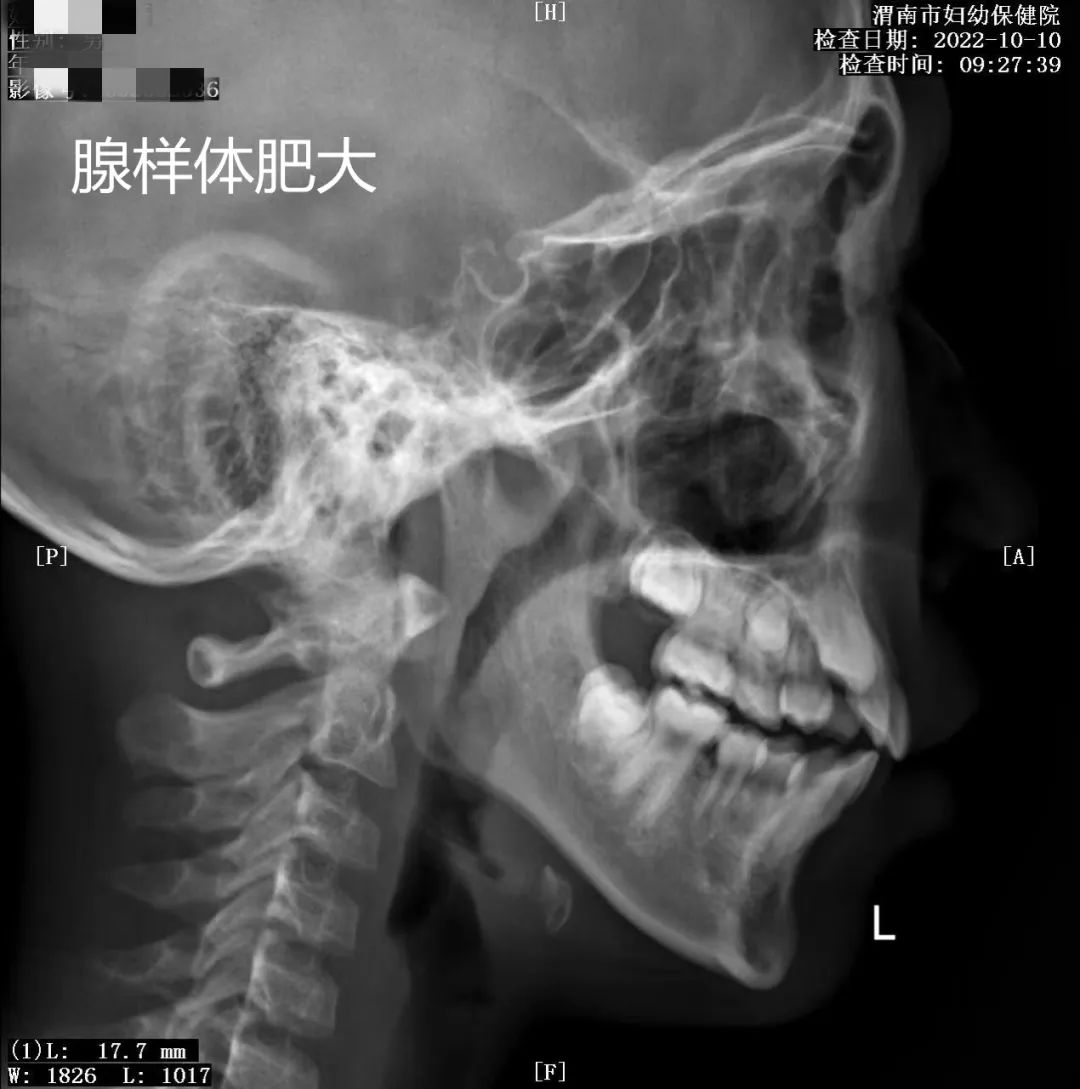

放射"摄影作品"